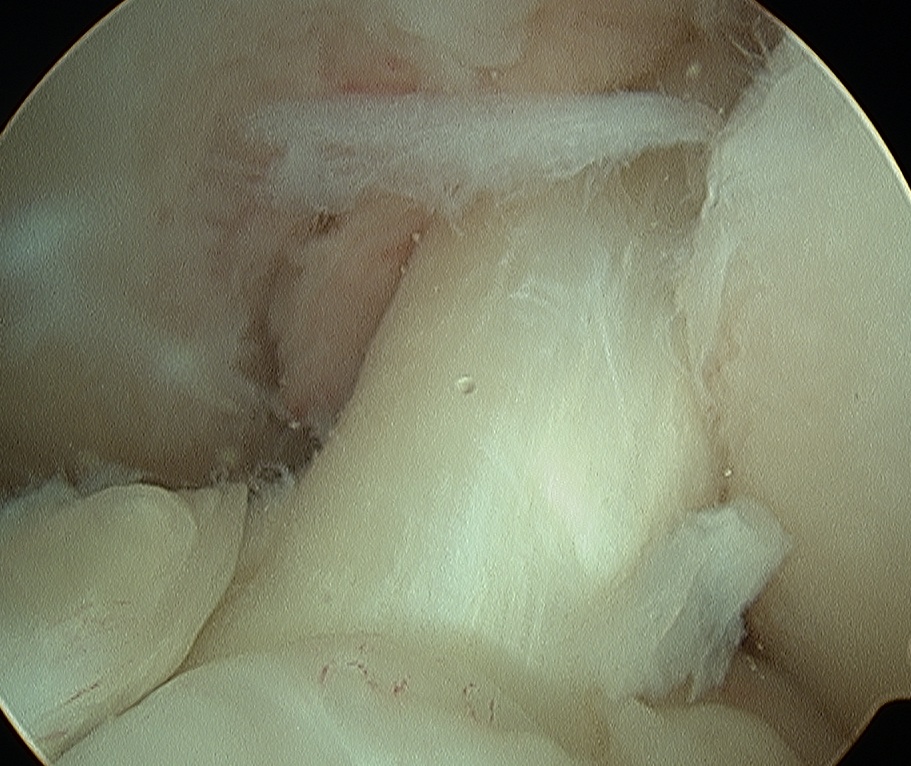

- can also look inside knee with scope to confirm insertion

Ream tibial and femoral tunnels

- outside in to preserve native ACL